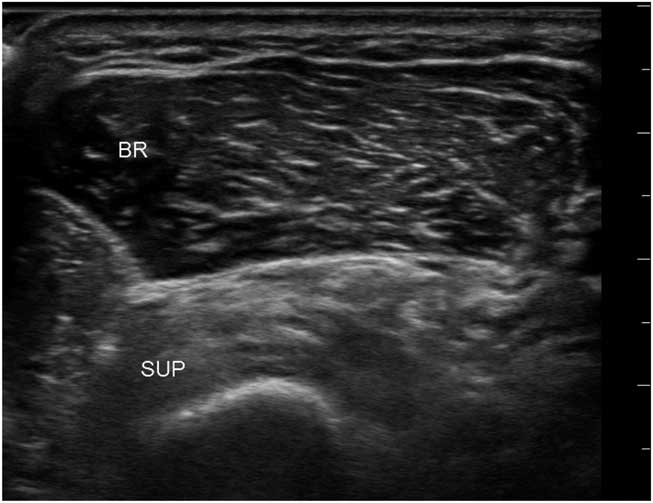

Figure 12 Transverse image of the proximal dorsomedial forearm showing the radius with an overlying supinator and brachialis muscle. The echogenicity of the supinator is clearly abnormal and compatible with selective denervation caused by a partial infraclavicular brachial plexus traction injury. BR=brachioradialis; SUP=supinator.